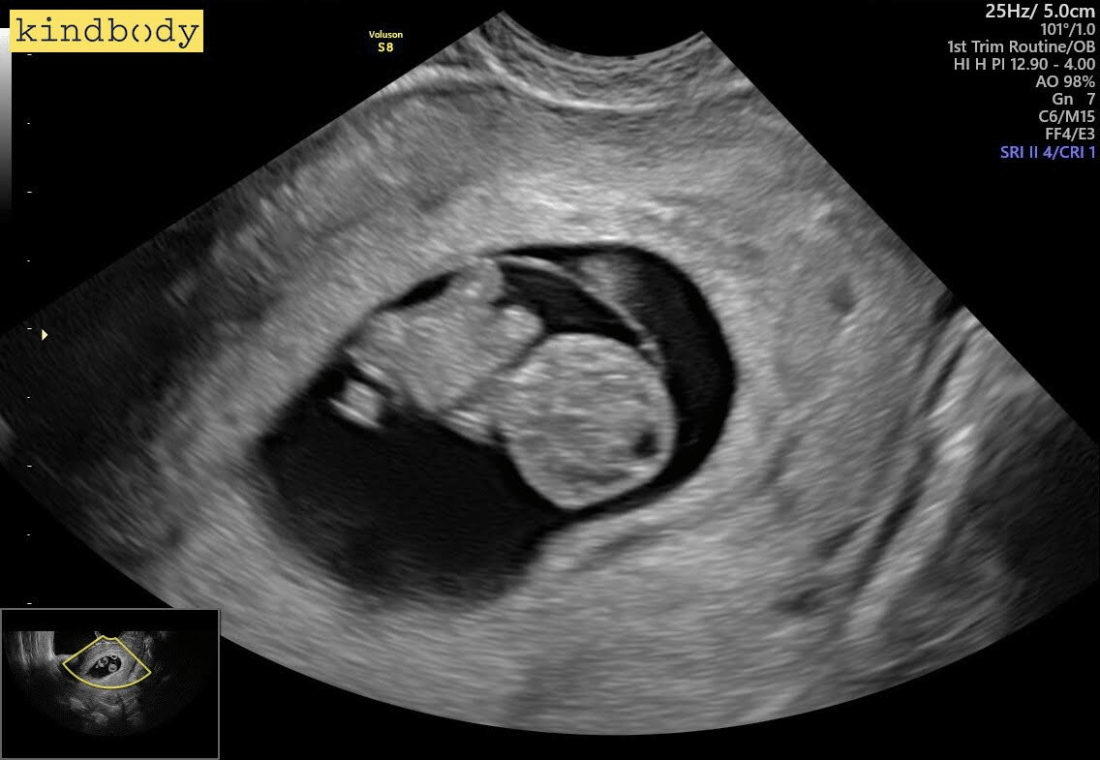

We were optimistic about our chance of a successful transfer, given our PGT-WGS screening, a good embryo grade, and a history of successful transfers — but that didn’t make the wait any less anxious.  But a few weeks later, we got a positive test, and a clean ultrasound a few weeks after that — the transfer had been successful.